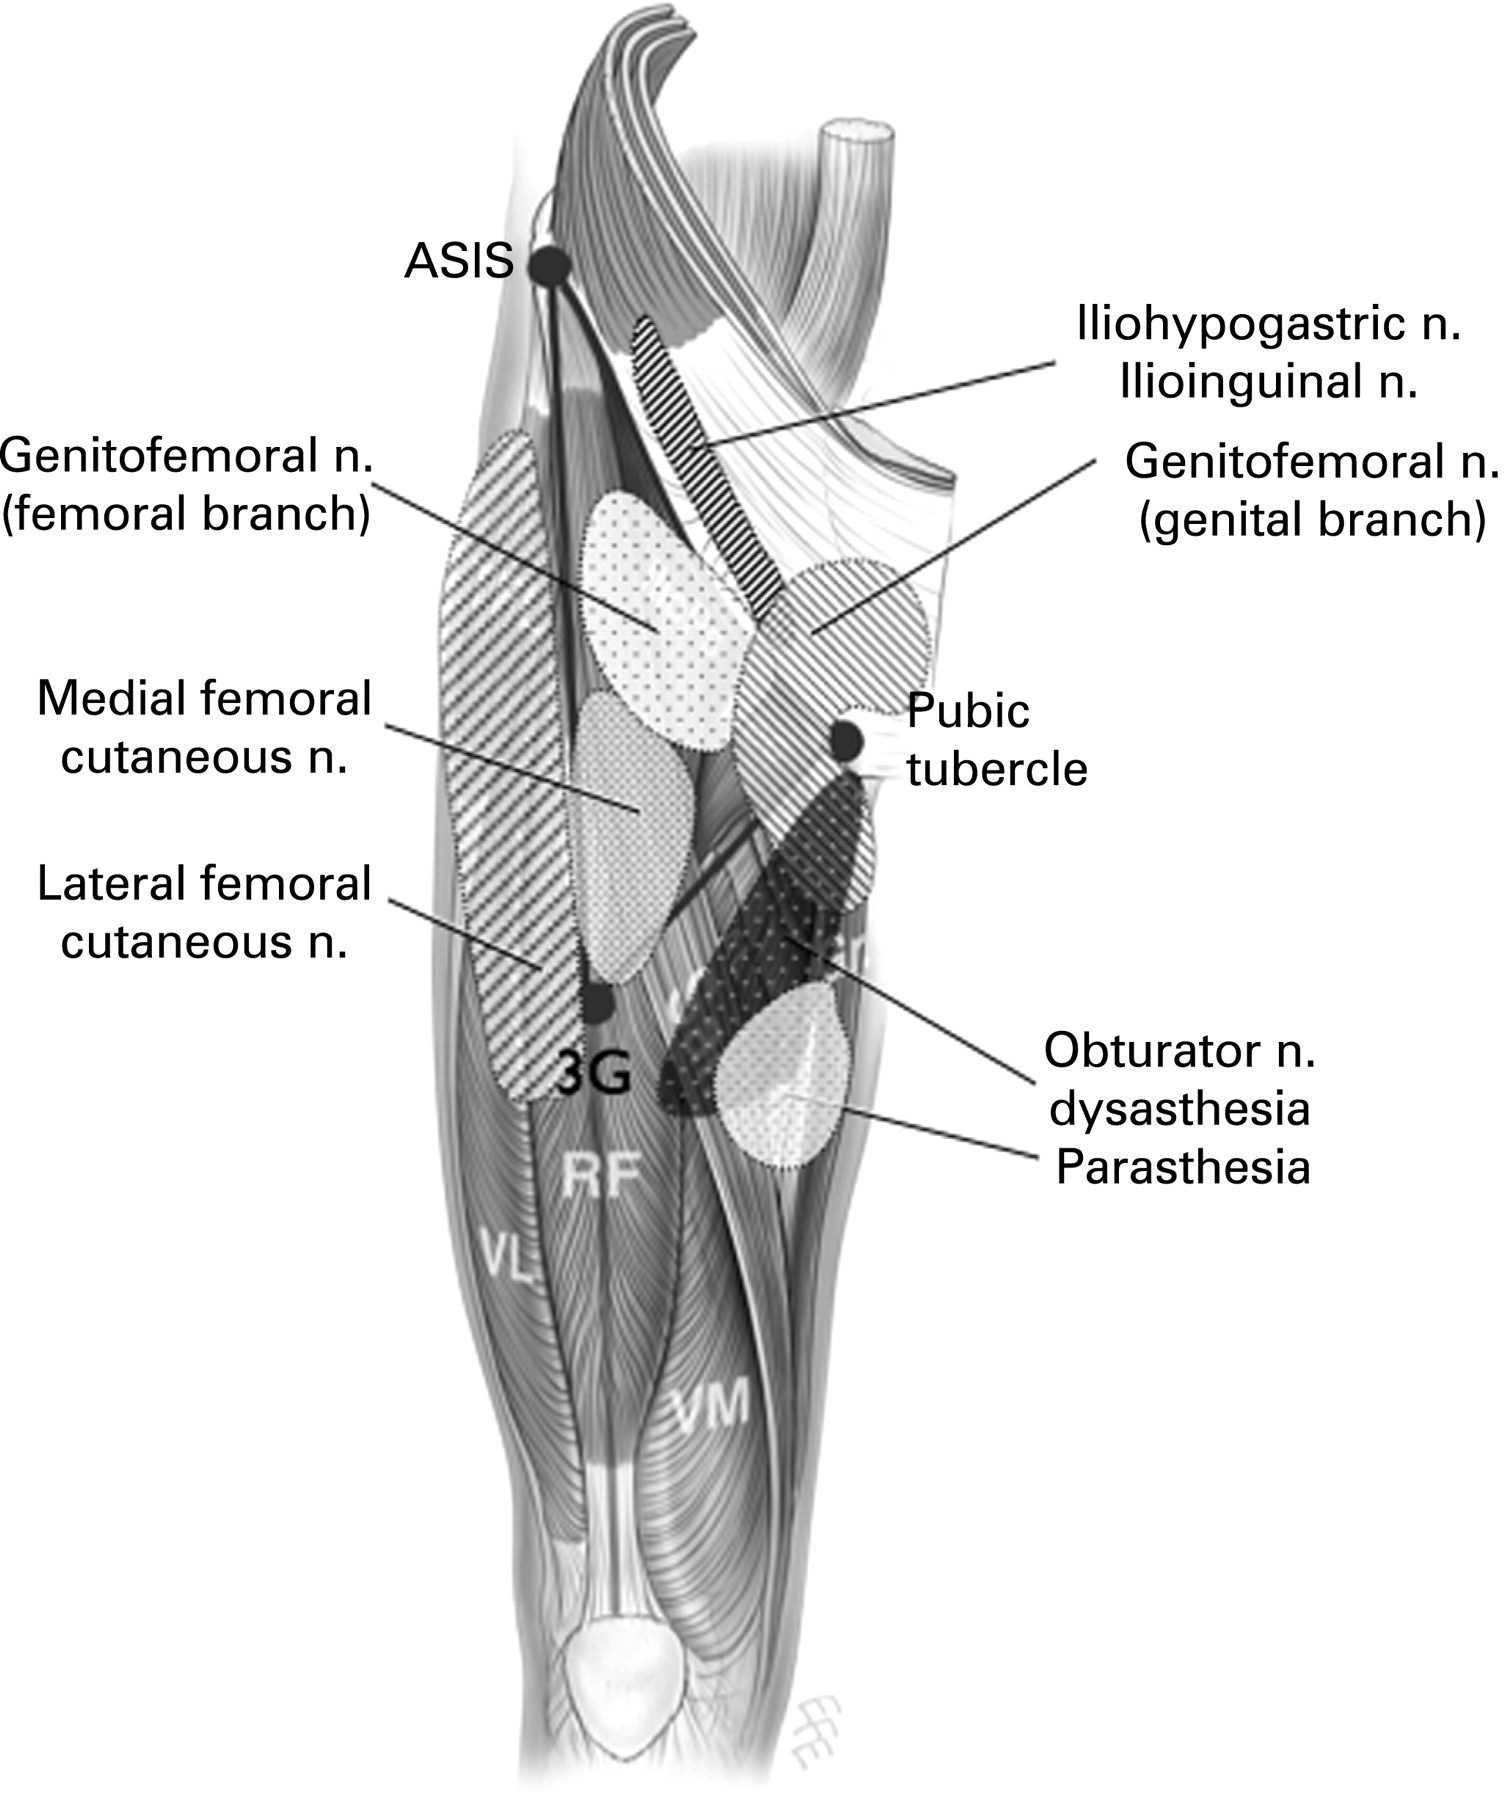

Groin adductor gracilis stomach lower The groin triangle: a patho-anatomical approach to the diagnosis of Groin anatomy nerves area innervation fig

Groin muscles hip inguinal mizz kidal gluteus medius minimus piriformis healthjadeGroin pulled heal adductor Groin anatomy deep supply fig vesselsAnatomy of the groin.

Groin muscle anatomyGroin pain triangle sports athletes approach chronic figure anatomical diagnosis patho larger version .